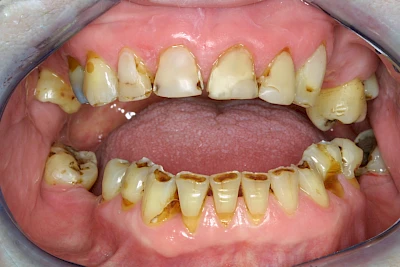

Über die Zeit können verschiedene Prozesse die Zahnhartsubstanzen aufzehren:

- Abnutzung durch Kauen (Abrasion) oder duch durch übermäßiges Knirschen bzw. Pressen (Attrition)

- Säurebedingte Auswaschung (Erosion)

- Knirschen bzw. Pressen und ungünstige Putztechnik (Druck): keilförmige Defekte

Auswaschung (Erosion) dagegen ist eine Verschleißerscheinung der Zähne aufgrund von immer wiederkehrenden Säureangriffen durch die Nahrung, verstärkt zum Beispiel durch den Genuss säurehaltiger Getränke oder Speisen. Auch bei Menschen mit einer Essstörung (z. B. Bulimie) können die Zähne durch die Magensäure ausgewaschen erscheinen.

Eine Sonderform sind sogenannte keilförmige Defekte im Bereich der Zahnhälse. Hier geht man davon aus, dass Knirschen und Pressen in Kombination mit falschen Putzgewohnheiten (zu hoher Putzdruck, Verwendung von Zahnpasta mit hohen Abrasionswerten) eine Rolle spielen.